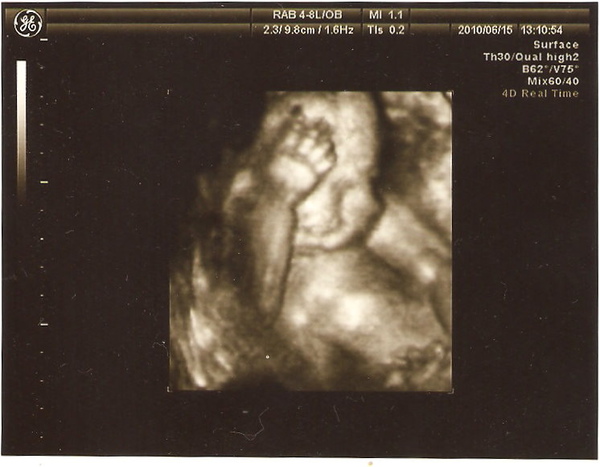

十指健全

這是他的腳,睡到蹺腳~